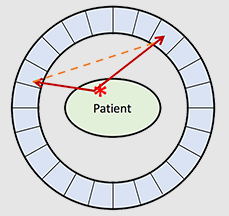

What is a scatter coincidence?

This is when the one of the photons emitted from an annihilation event interacts with something in its path to the intended detectors – causes it to change directions and affects the original line of response → a false line of response is drawn

This will show up on our image as an annihilation event that happened outside of where it is supposed to be

What happens to the energy of the photons if a scatter coincidence happens?

If one of the photons interacts with something on its path to the intended detector, it will lose energy and it may be rejected by the detector as an annihilation event entirely – detector wants two 511 keV photons